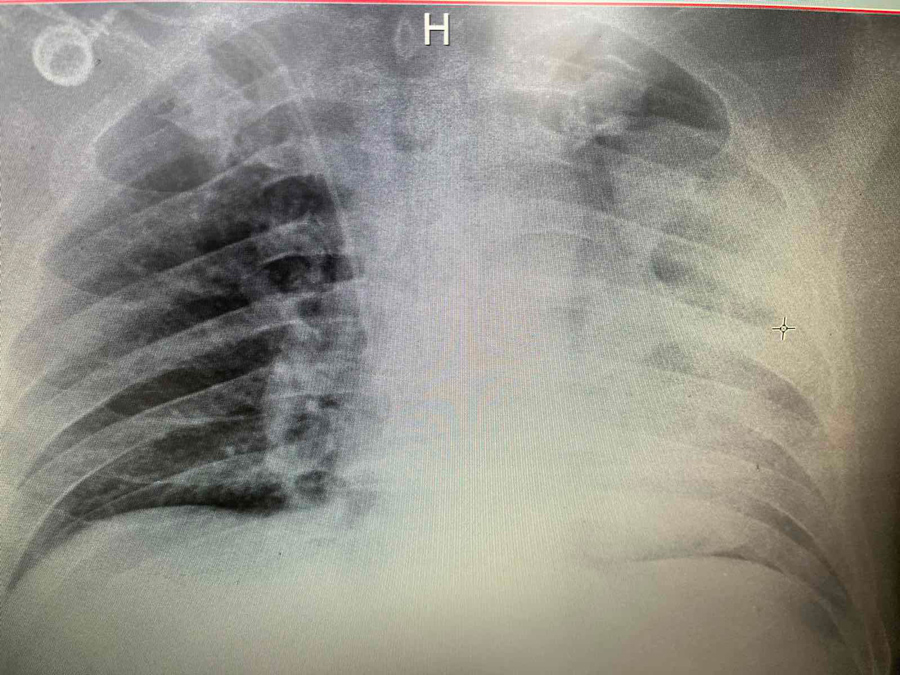

Фотографии, демонстрирующие обнаруженное усиление легочного рисунка

Раздел: Фотодневник открытий